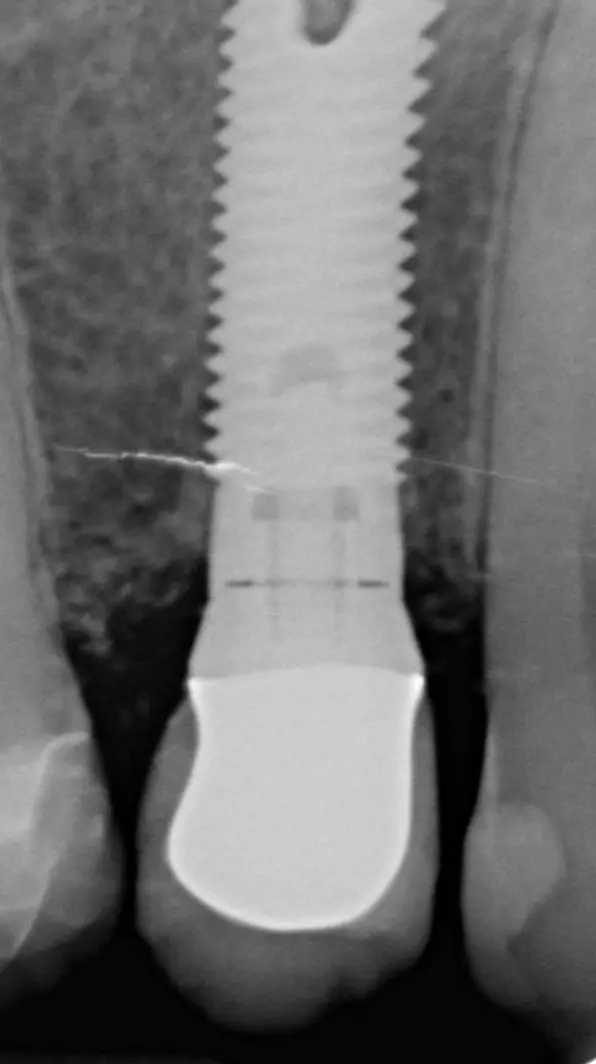

Der Emergenzwinkel ist definiert als der Winkel, der sich aus der Schleimhaut zugewandten Abutmentoberfläche und der Implantatlängsachse ergibt (Abb. 1). Das Emergenzprofil ist definiert als die Kontur des der Mukosa zugewandten Abutmentanteils (Abb. 2).

Wenn zusätzlich zu dem Emergenzwinkel auch noch das Emergenzprofil in die Analyse einbezogen wurde, zeigte sich bei einem Emergenzwinkel >30° in Kombination mit einem konvexen Emergenzprofil (Abb. 3) auf mindestens einer interproximalen Seite eine signifikante Erhöhung der Periimplantitisprävalenz von 37,8% (p=0,003).

30° in Kombination mit einem konvexen Emergenzprofil.“ class=“wp-image-26382″/>

30° in Kombination mit einem konvexen Emergenzprofil.“ class=“wp-image-26383″/>

Auch diese signifikante Erhöhung des Periimplantitisrisikos bezieht sich auf Bone-Level Implantate, nicht aber auf Tissue-Level Implantate. Es scheint, dass die reduzierte Hygienefähigkeit und die damit verbundene erhöhte Plaqueakkumulation für die erhöhte Periimplantitisprävalenz von Implantaten, die mit Abutments mit weitem Emergenzwinkel und konvexem Emergenzprofil versorgt sind, verantwortlich sind [11].